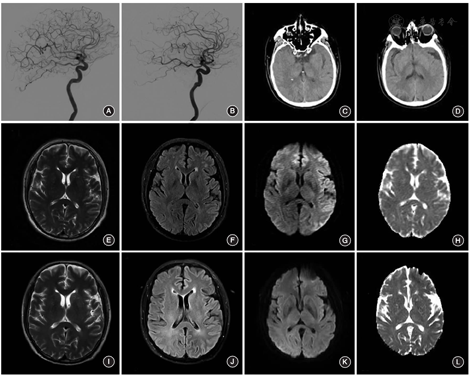

例1 女,59岁。因"发现颅内动脉瘤3个月"入院。患者3个月前无明显诱因突然出现头晕、视物旋转,当地医院头颅MR血管成像(MRA)检查提示左侧颈内动脉动脉瘤,经对症治疗2周症状完全缓解。为进一步治疗动脉瘤入院。既往无原发性高血压、心脏病、糖尿病病史。入院体检:血压133/86 mm Hg(1 mm Hg=0.133 kPa),神经系统查体未见明显异常。为明确诊断并制定进一步治疗方案,在无明显禁忌证的情况下,于入院后第3天行全脑数字减影血管造影(DSA),发现双侧眼动脉段动脉瘤,共使用碘克沙醇100 ml(含碘量为320 mg/ml)。手术过程顺利,术后患者未诉明显不适。于入院后第7天行双侧眼动脉段动脉瘤栓塞术,共使用320 mg/ml的碘克沙醇200 ml。患者术中生命体征平稳,苏醒后未诉不适。术后5 h,患者出现言语不利。体检:意识清醒,混合性失语,余神经系统检查未见明显异常;头颅MRI未见明显异常。给予维持血压、改善循环及营养神经等治疗。术后20 h,患者病情进展,出现意识模糊,双眼向左侧凝视,头颅CT未见明显出血(图1A);DSA检查未见脑血管闭塞(图1B)。术后32 h,患者突发四肢抽搐,给予镇静、抗癫痫、补液等治疗;头颅MRI T2加权成像可见左侧额、顶叶脑沟较对侧变浅,T2-液体衰减反转恢复序列(FLAIR)及弥散加权成像(DWI)序列可见双侧皮质信号不均匀增高,以左侧额、顶及颞叶为著,呈"花边征"表现;表观弥散系数(apparent diffusion coefficient,ADC)呈等信号(图1C~F)。常规实验室检查未见明显异常,脑脊液压力正常、细胞学检查正常、蛋白含量稍增高。结合患者临床表现及影像学特征,考虑为CIE。给予甲强龙、丙戊酸钠、充分补液、稳定血压等治疗。术后4 d,患者意识恢复,肢体抽搐未再发。体检:意识清楚,言语欠流利,四肢肌力Ⅳ级,双侧巴彬斯基征(-)。术后8 d,患者的言语不利明显好转,头颅MRI显示左侧半球皮质异常信号消失(图1G~J)。术后30 d患者出院。术后6个月随访,症状完全恢复,头颅MRI未见明显异常。

此外,该2例患者DWI均显示"花边征"的特点,而既往文献报道中少见;与其他文献报道一致的是,影像学表现为以T2WI、T2-FLAIR、DWI为主的高信号,ADC无明显异常信号,且完全可逆[6]。受累区域与血管内操作的血管分布区一致,提示CIE与血管内操作及对比剂直接相关。考虑到患者行颅内动脉瘤栓塞术前DSA检查均未出现过敏反应及其他不适,进一步提示局部对比剂浓度可能与CIE的关系更为密切,与既往认为的高渗对比剂更易诱发CIE的结论一致[7]。